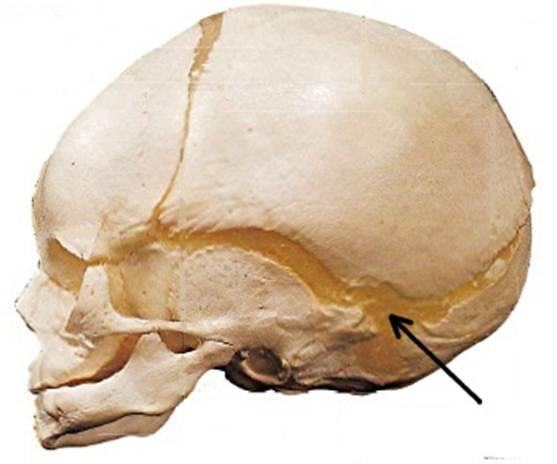

Структура и анатомия синдесмоза: научные иллюстрации